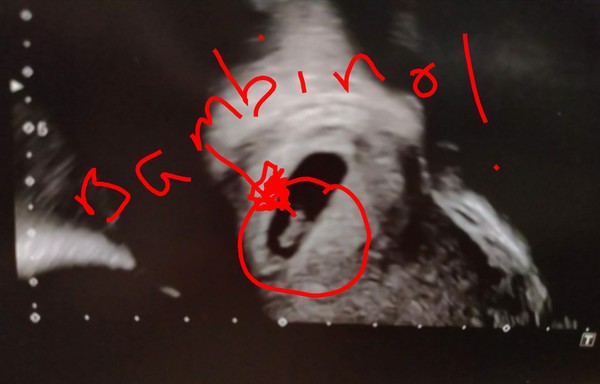

BambiOnIce80 · 18/02/2020 14:38

Ladies thank you so much for all your positive vibes 💓 🥰 It's been a busy little morning, but finally got time to sit still and update you all 👍 As you can see from the pic, we're in the 'so far, so good' category 😪 Sooooo relieved to see that little flicker of the heartbeat 😍 DP even shed a couple of tears, which was surprising (but lovely! 😊). He's currently working on a list of boy and girl names... I'll be reigning him in shortly! 😉 The nice thing about the scan was that the consultant was the same one that did our ET and she was so genuinely chuffed for us - it was quite touching 🥺 Oh, and @Lily999 it turns out that my little lower right-sided ache isn't anything to do with the bambino because it's implanted on the left of my uterus! 😳 The doc said I've got a cyst on my right ovary (perfectly normal after all the meds we've been on for a fresh cycle), so that's probably what my dull ache has been... which means I've hardly had any genuine cramping really! 🤷‍♀️